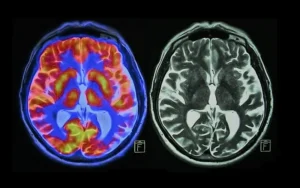

“Cuando una persona se enfrenta a una amenaza percibida, el hipotálamo, que es una región pequeña en la base del cerebro, activa un sistema de alarma en el cuerpo. Mediante señales nerviosas y hormonales, este sistema incita a las glándulas suprarrenales, que se encuentran encima de los riñones, a liberar una oleada de hormonas, como la adrenalina y el cortisol”.

Así, cuando el estrés se convierte en parte del día a día, se normaliza y se experimenta con mayor intensidad, se convierte en estrés crónico que se relaciona con el desarrollo y agravamiento de diversas enfermedades y padecimientos.

Lo anterior se explica ante la sobreexposición al cortisol y otras hormonas del estrés que alteran casi todos los procesos del cuerpo.